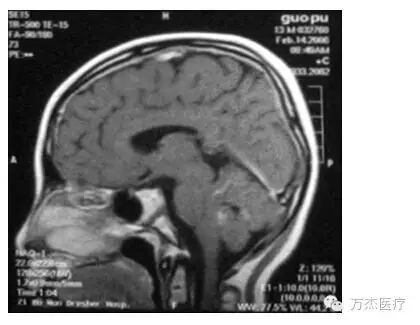

典型病例(髓母细胞瘤):

治疗结束时